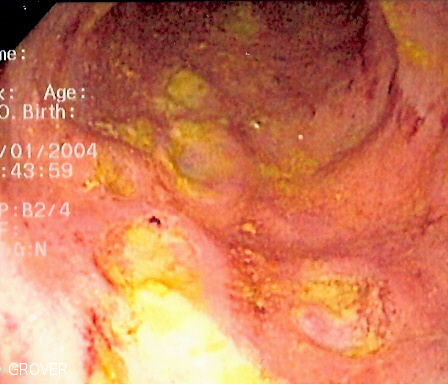

Endoscopic image of Crohn's colitis showing deep ulceration in sigmoid colon. Photo released into public domain on permission of patient. -- Samir धर्म 07:35, 2 June 2006 (UTC)

| current | 07:35, 2 June 2006 | 448×384 (47 KB) | Samir ( Talk | contribs) | ( Endoscopic image of Crohn's colitis showing deep ulceration in sigmoid colon. Photo released into public domain on permission of patient. -- ~~~~) |